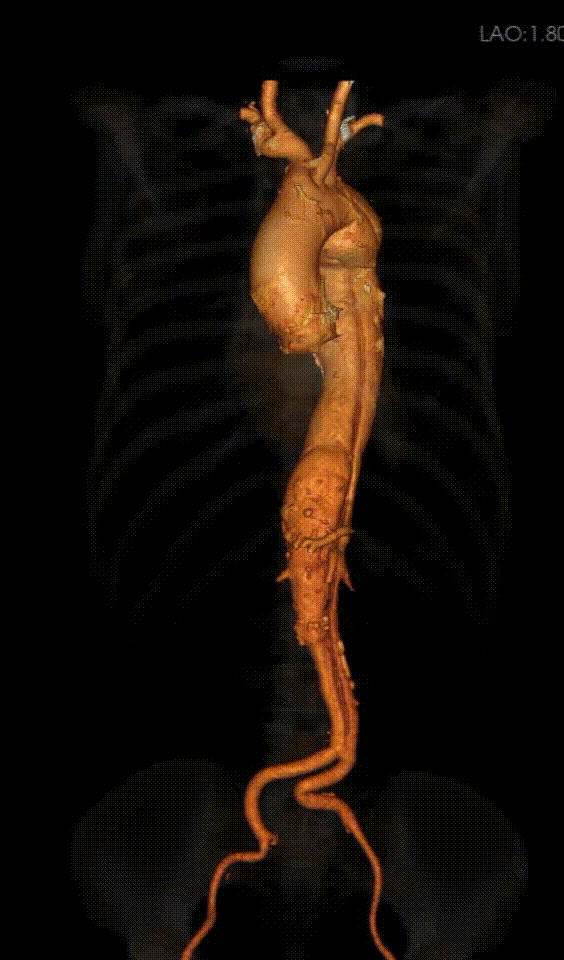

患者为 72 岁女性,因 “发作胸痛三天” 急诊入院。CTA检查结果显示为陈旧性主动脉夹层。夹层向前逆撕累及弓部,范围从左侧锁骨下动脉开口后缘远端延伸至腹主动脉分叉上方。分支血管受累:腹腔干、肠系膜上动脉及左肾动脉由真腔供血,右侧肾动脉由假腔供血。

双侧入路扭曲纤细,最细处右侧髂外直径6.5mm,左侧6mm;降主及腹主真腔严重受压,管腔狭窄。

从右侧股动脉入路,使用超滑导丝进入真腔,置入金标猪尾导管造影,再次造影明确夹层真腔位置、形态,可见腹主动脉及降主动脉真腔处多处严重狭窄受压,假腔呈瘤样扩张并累及左侧锁骨下动脉。